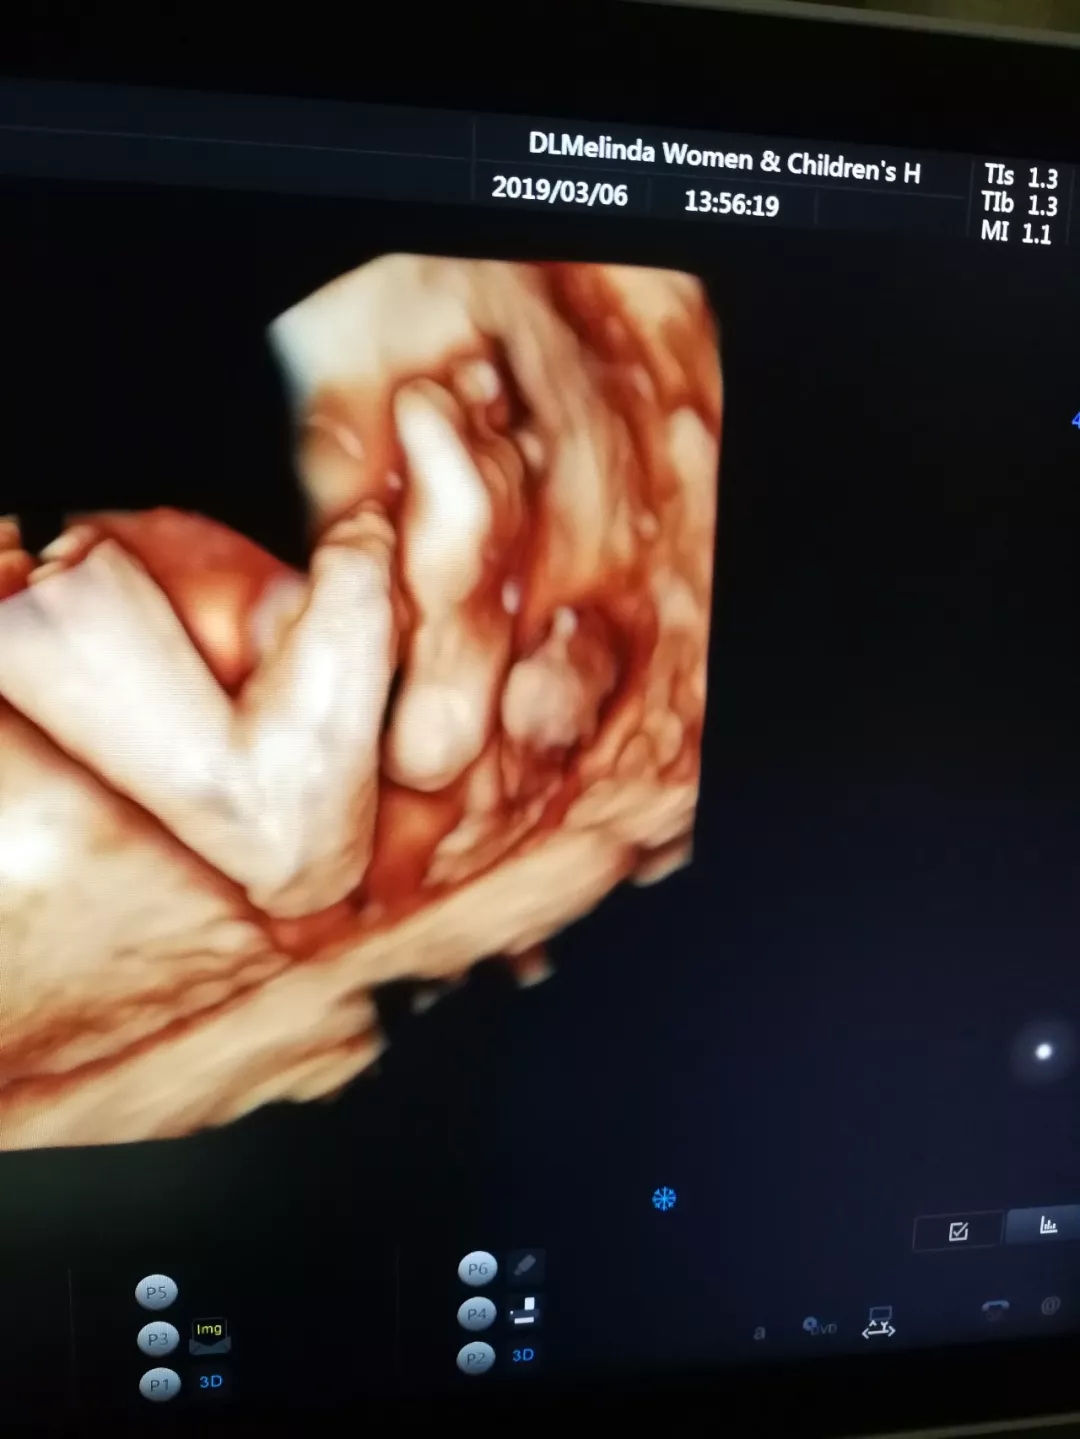

“妈妈,告诉您哦~我“十八般武艺”样样都精通

当您感觉到胎动的时候,有可能是我刚睡醒,在伸伸胳膊、扭扭身子、蹬蹬腿,但我的绝招是,我能在您的肚子里练拳,练侧踢,没事还能来个前空翻、后空翻呢。我最喜爱的玩具是我的脐带,我可以抓着它绕圈圈,可是有时候玩着玩着,脐带就会缠在我的脖子上,但是妈妈您不用担心,我会一点点把脐带绕回去哒~”

Ⅴ.赠送胎儿写真集

检查后赠送宝宝高清写真照片,给准爸妈和宝宝留下美好瞬间的纪念。

Ⅵ.可拍摄动态视频

只是记录宝宝在妈妈肚子里的一举一动,也是宝宝出演的首部“微电影”。